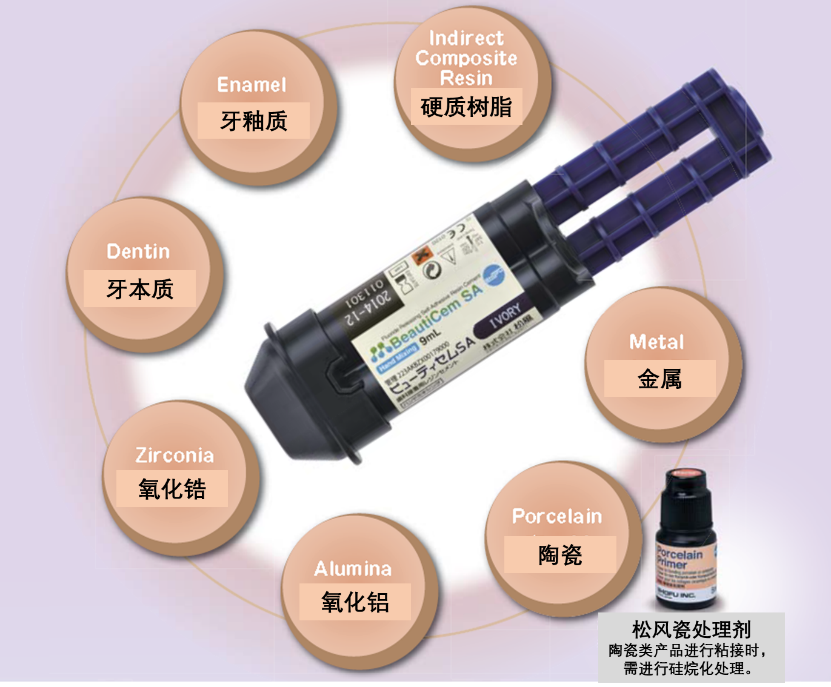

0 1产品特性适用范畴广

内含应对多种材料以及牙体组织的处理成分,可对多种材质多种类型的修复体进行高强度粘接。

适用范围:

• 全瓷修复体:单冠,冠桥,嵌体,高嵌体以及嵌体冠(比如松风Vintage ZR);

• 金属烤瓷冠:单冠,冠桥(比如松风 Vintage, Vintage Halo)

• 金属修复体:贵金属,非贵金属以及各种金属合金,包括钛在内的单冠,冠桥,桩核等。

• 各种CAD/CAM 修复体:氧化锆、树脂基陶瓷,铸瓷(需进行匹配的瓷处理)

• 树脂或硬质树脂修复体:嵌体,高嵌体,单冠等。(比如松风聚合瓷Ceramage)

• 各种桩核修复体:金属桩核,树脂桩核,纤维桩(高精密度)等。